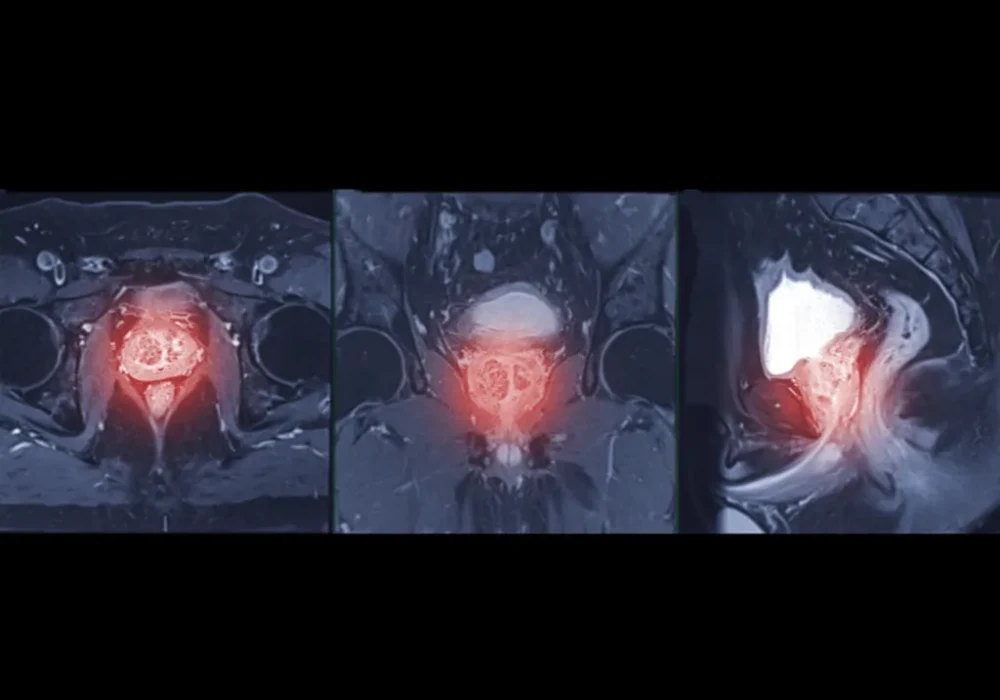

Imaging included standard components of mpMRI. Maps derived from diffusion and perfusion sequences were prepared with consistent preprocessing and registration to limit site effects. Radiologists outlined lesions, avoiding areas such as necrosis or haemorrhage, and transferred the same outlines across all maps. A simple, reproducible clustering step then grouped voxels into three habitats based on their diffusion and perfusion characteristics. For each lesion, the resulting habitat map showed where each subregion lay and how much space it occupied, turning complex images into a concise, interpretable profile that could be compared with surgical pathology.

Three distinct habitats emerged repeatedly across lesions. One subregion, referred to here as Habitat 1, showed the combination of more restricted diffusion and greater structural complexity on the MRI-derived maps. Another, Habitat 2, tended to display the opposite pattern, while Habitat 3 sat between them. When these habitat maps were aligned with post-surgical pathology, a clear pattern appeared. High-grade cancers contained a larger share of Habitat 1, whereas low to medium grade cancers were more commonly composed of Habitat 2.

This link between anatomy on mpMRI and pathology after surgery is clinically meaningful. Rather than relying on a single average value for a whole lesion, habitat imaging preserved intratumoural differences and connected them to grade. In the training data, Habitat 1 correctly identified high-grade disease in the great majority of relevant cases. Although the other subregions carried useful context, their association with high-grade pathology was weaker. These observations supported using the proportion of Habitat 1 as a concise imaging marker of aggressiveness that could be combined with routine clinical-imaging information.

Importantly, the habitat maps remained grounded in images that clinicians already use. The process did not demand exotic acquisition or opaque modelling. It repackaged familiar sequences into a spatial summary that highlighted the parts of a tumour most likely to host high-grade disease, providing a visual cue that complements radiologist assessment and could inform targeted sampling or treatment planning.